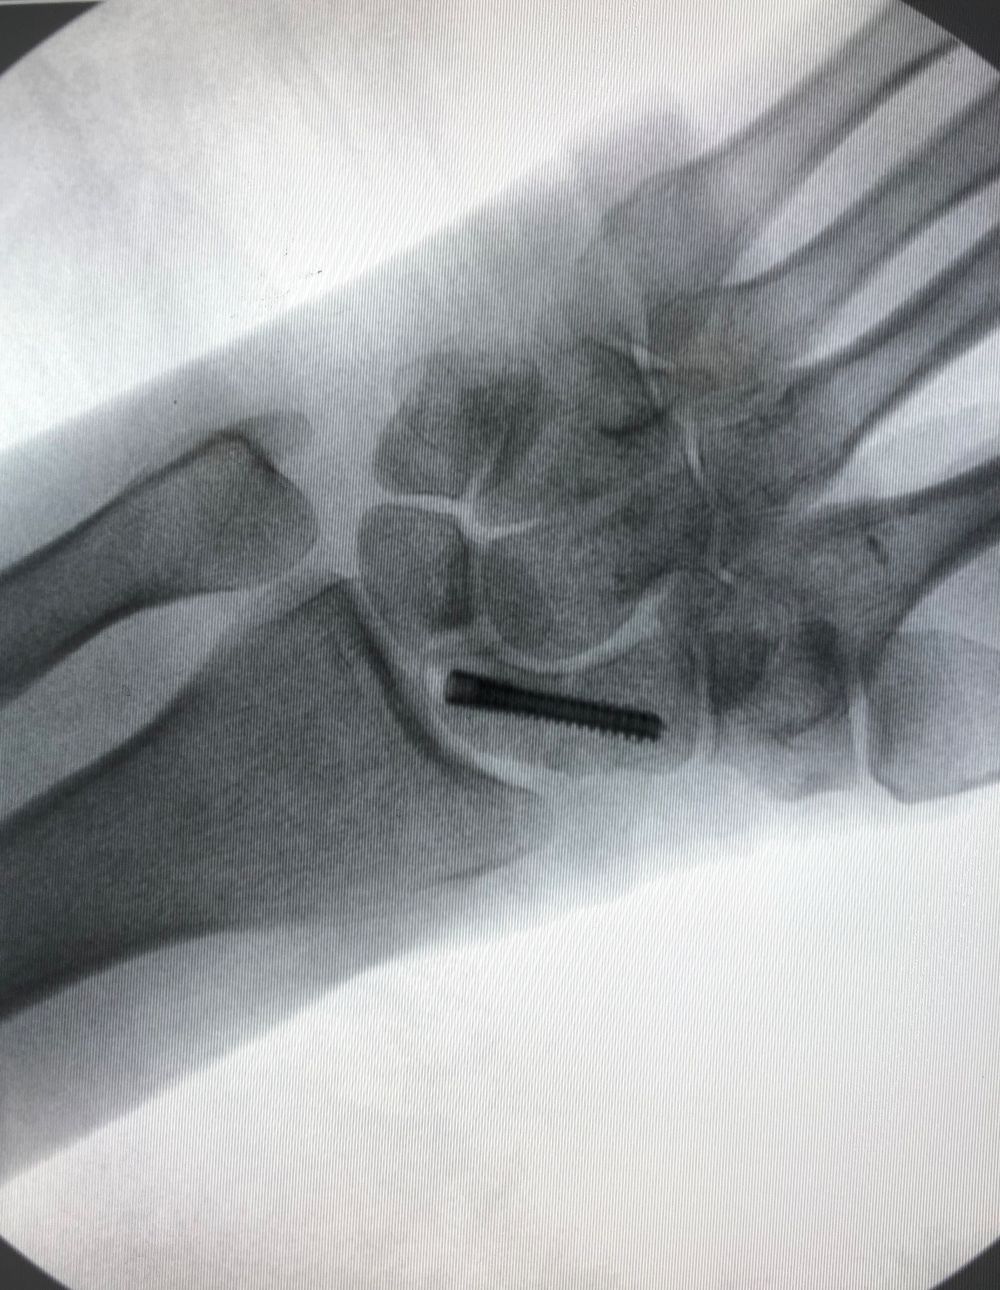

El tratamiento puede ser conservador o quirúrgico.  Dentro del tratamiento quirúrgico existen diferentes técnicas (cirugía percutánea (Figura 3), cirugía asistida por artroscopia, cirugía abierta, …), (Figura 4). Así mismo, el material utilizado puede variar también (tornillos, agujas,…).  Su Cirujano de Mano, el Dr. Polo, le recomendará la mejor opción en su caso concreto.

Figura 3 - Cirugía percutánea de fractura de escafoides. Dr Polo.